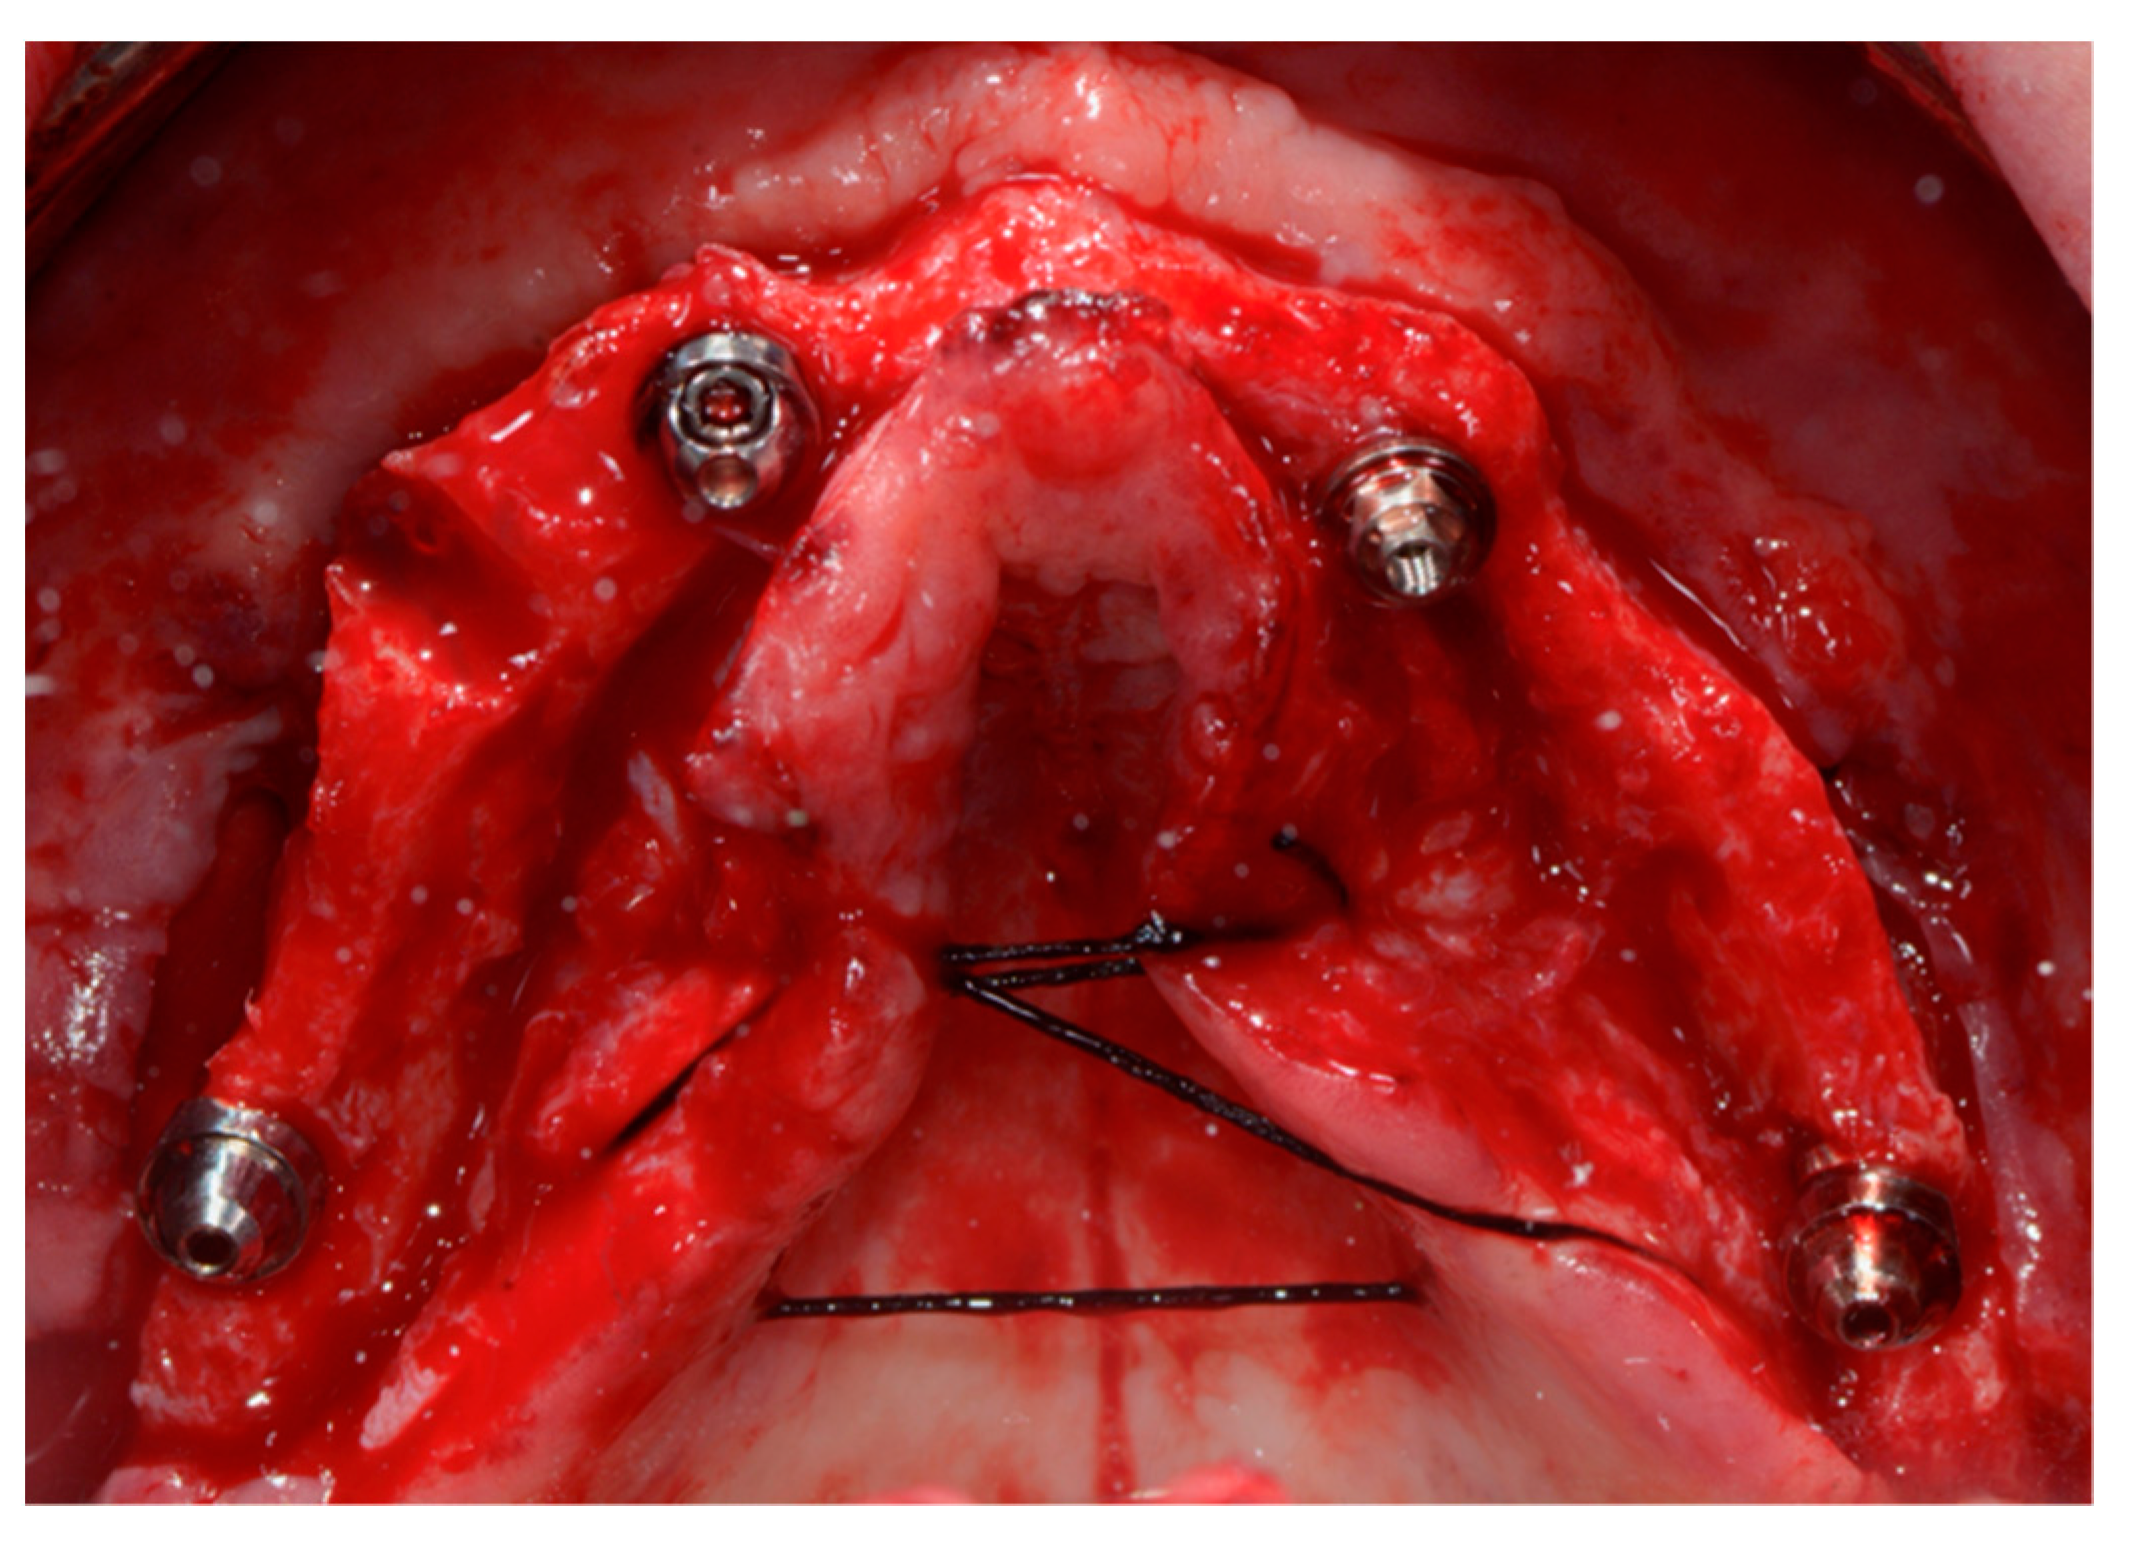

2.2.4. Fourth Appointment (Traditional Protocol): Surgical Phase and Immediate Loading Prosthesis

2.2.7. Fifth Appointment (Digital Protocol): Surgical Phase and Immediate Loading Prosthesis

2.2.8. Final Prosthesis